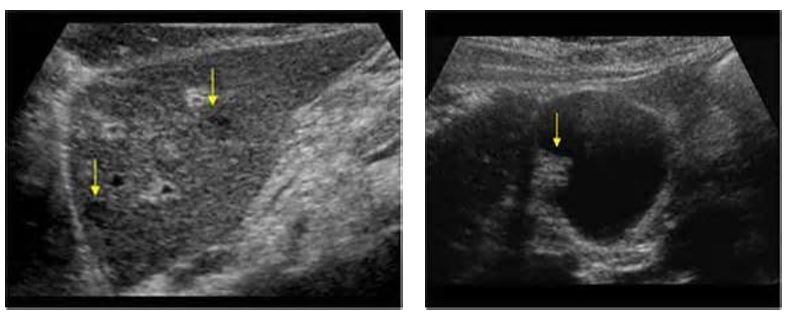

what is this showing?

Choledocholithiasis

what are these pics showing?

Cholesterol polyps

What is the most common benign tumor of the gallbladder?

Cholesterol polyps

Benign neoplasms that have a lower premalignant potential compared to colonic adenomas.

typically solitary lesions

to be pedunculated, meaning they are attached by a stalk

Smaller adenomas are generally homogeneously hyperechoic

Larger adenomas tend to become more heterogeneous

Adenoma of GB